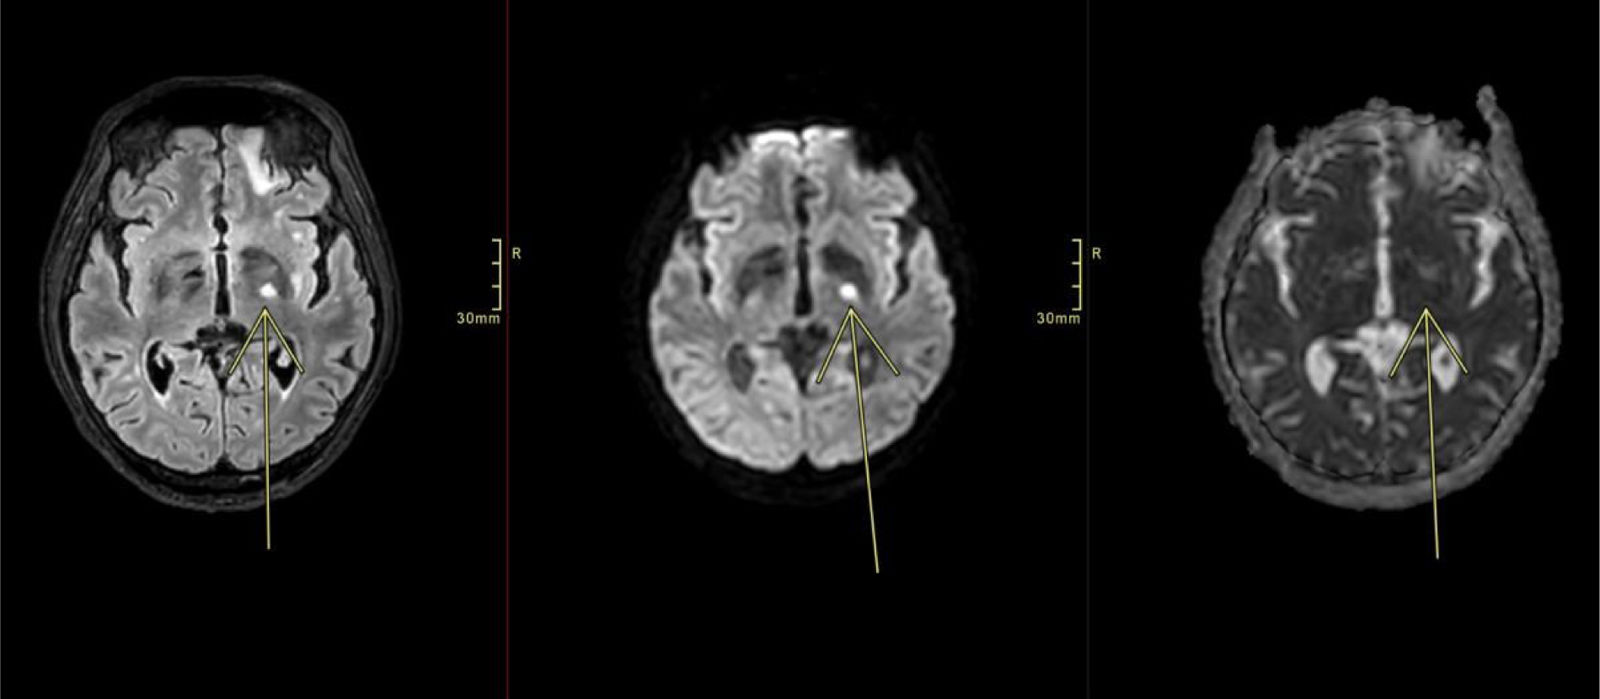

Multiple strokes as a presentation of neurosyphilis in a patient with HIV infection

Medicina Clínica (English Edition) Multiple strokes as a presentation of neurosyphilis in a patient with HIV infect...